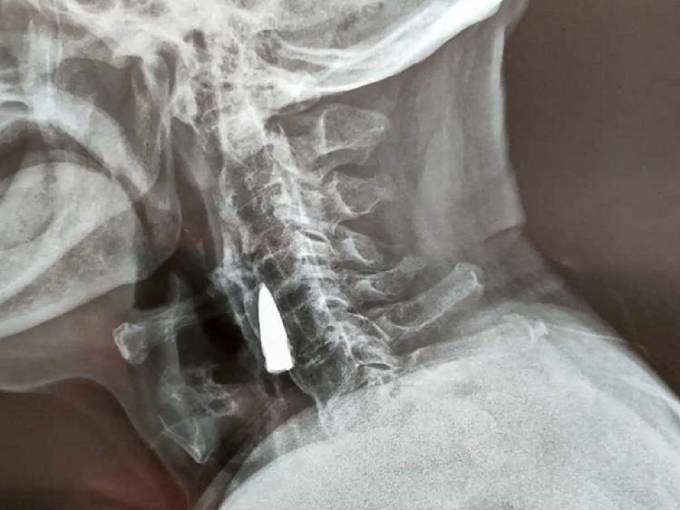

Viên đạn mắc trong cổ ông Zhao qua hình chụp x-quang. Ảnh: Oddity Central

Sau khi nghe Zhao kể về cú ngã, các bác sĩ đề nghị chụp x-quang để đảm bảo ông không bị thương nặng ở cổ. Tuy nhiên, thay vì phát hiện vết rạn xương, kết quả cho thấy có vật lạ mắc ở cổ bệnh nhân. Vật này sau đó được xác định là một viên đạn cũ.

Sau khi kiểm tra phim chụp x-quang, các bác sĩ nói với ông Zhao He và gia đình rằng viên đạn nằm gần một số mạch máu lớn, và do nó không gây ra vấn đề gì cho bệnh nhân nên tốt nhất là không can thiệp.